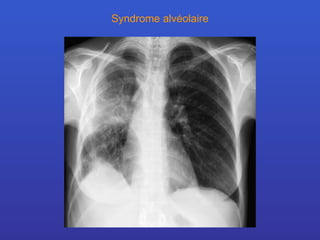

Syndromes radiologiques Syndrome alvéolaire

Définition: Le syndrome alvéolaire se définit par une atteinte des espaces aériens distaux, au cœur du lobule pulmonaire. Critère  radiologiques répartition systématisée lobaire ou segmentaire limites floues tendance à la confluence bronchogramme et/ou alvéologramme aérique répartition en aile de papillon

Syndrome alvéolaire pneumonie franche lobaire

Syndrome alvéolaire